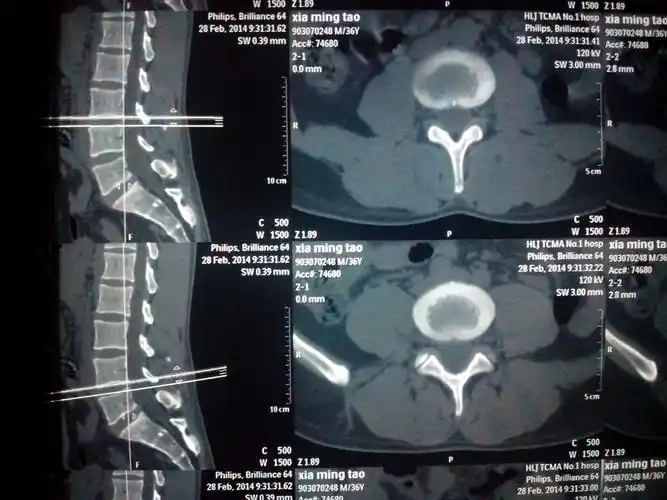

腰突

ct,x光,核磁共振,谁更适合腰突症检查,你都了解吗?